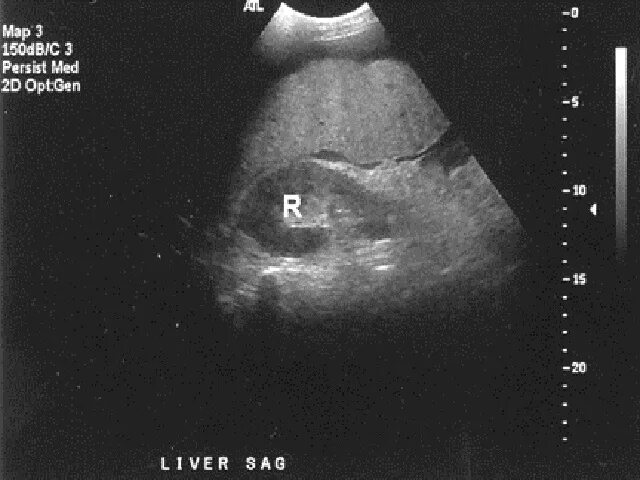

Асцит в малом тазу